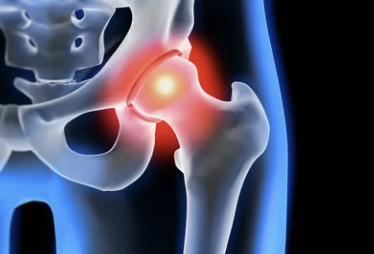

4. 관절 및 골반 질환 관련 원인

✅ 고관절염, 천장관절증후군, 꼬리뼈 통증

| 고관절염 | 관절연골 퇴행 또는 염증 | 엉덩이 앞·옆쪽 통증, 다리 벌리기 어려움 |